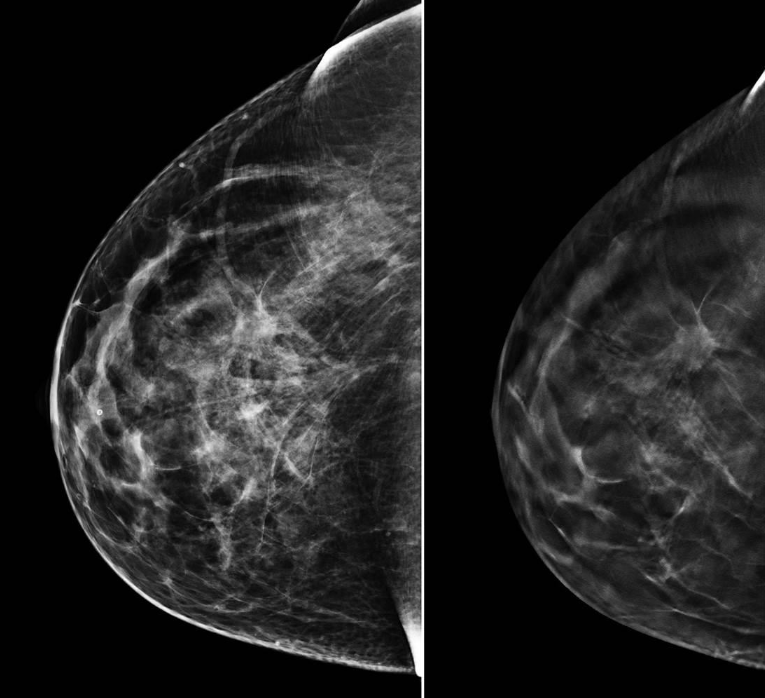

what is mammography?

specialized low dose x-ray image of breast

special detector used to accentuate contrast in breast

what do you need to see in breast mammography?

glandular and fatty tissues

skin line of breast